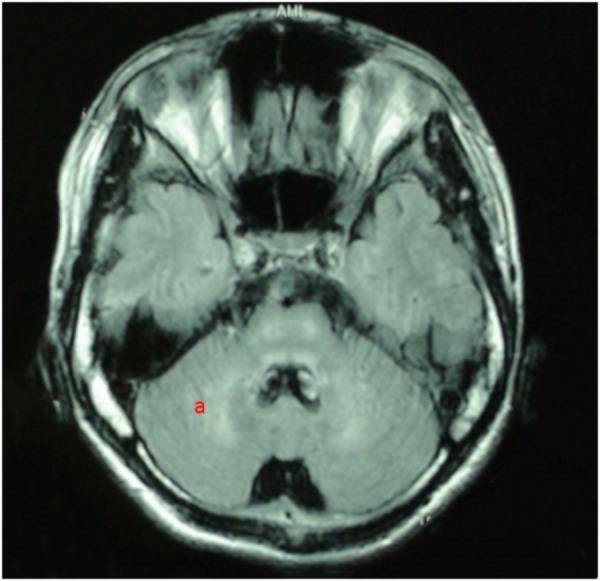

Wilson's disease (WD) is an inborn copper metabolism disease. Sex differences in clinical features of WD patients have been reported; however, the effect of sex on brain MRI is still unclear, especially for Chinese WD patients. Therefore, we aimed to examine sex differences in clinical correlates and brain MRI changes in WD patients in a Chinese Han population. 535 WD patients were enrolled and underwent MRI scanning. These patients were subdivided by the clinical symptoms, Kayser-Fleischer (K-F) rings, laboratory tests and sex. The mean age of onset and diagnosis, disease latency, localization of brain MRI lesions, and the level of copper metabolism were compared between male and female patients. The neuropsychiatric form (452 and 84.5%) was the most common subtype. Compared to female patients, male patients had a higher percentage in three clinical forms: neuropsychiatric form (263 and 58.2%), hepatic form (41 and 59.4%), and presymptomatic form (10 and 71.4%). In the neuropsychiatric form, male patients had the earlier age of onset and definitive diagnosis, and shorter time of disease latency than female patients. Putamen was the most common site for lesions in brain MRI of three groups. In the hepatic form, more male patients showed the ventricular widening than female patients (14/41 vs. 3/28; < 0.05). The level of serum ceruloplasmin and copper of WD patients with neuropsychiatric form was higher than that of male patients with hepatic or presymptomatic form. In women, however, patients of presymptomatic form have the highest level of the ceruloplasmin, and the level of serum copper in hepatic patients was highest. Our findings suggest sex differences in the percentage of three clinical forms. Meanwhile, the mean age of onset and diagnosis of female was higher than male, also happened in the disease latency. Only in the hepatic form, there was a sex difference in the ventricular widening.

威尔逊病(WD)是一种先天性铜代谢疾病。已有报道称WD患者的临床特征存在性别差异;然而,性别对脑部MRI的影响仍不明确,尤其是对于中国WD患者。因此,我们旨在研究中国汉族WD患者临床相关性和脑部MRI变化的性别差异。招募了535例WD患者并进行了MRI扫描。这些患者根据临床症状、凯泽-弗莱舍尔(K-F)环、实验室检查和性别进行了细分。比较了男性和女性患者的平均发病年龄和诊断年龄、疾病潜伏期、脑部MRI病变的定位以及铜代谢水平。神经精神型(452例,占84.5%)是最常见的亚型。与女性患者相比,男性患者在三种临床类型中的比例更高:神经精神型(263例,占58.2%)、肝型(41例,占59.4%)和症状前型(10例,占71.4%)。在神经精神型中,男性患者的发病年龄和确诊年龄更早,疾病潜伏期比女性患者短。壳核是三组脑部MRI中最常见的病变部位。在肝型中,男性患者出现脑室增宽的比例高于女性患者(14/41比3/28;<0.05)。神经精神型WD患者的血清铜蓝蛋白和铜水平高于肝型或症状前型男性患者。然而,在女性中,症状前型患者的铜蓝蛋白水平最高,肝型患者的血清铜水平最高。我们的研究结果表明三种临床类型的比例存在性别差异。同时,女性的平均发病年龄和诊断年龄高于男性,疾病潜伏期也是如此。仅在肝型中,脑室增宽存在性别差异。